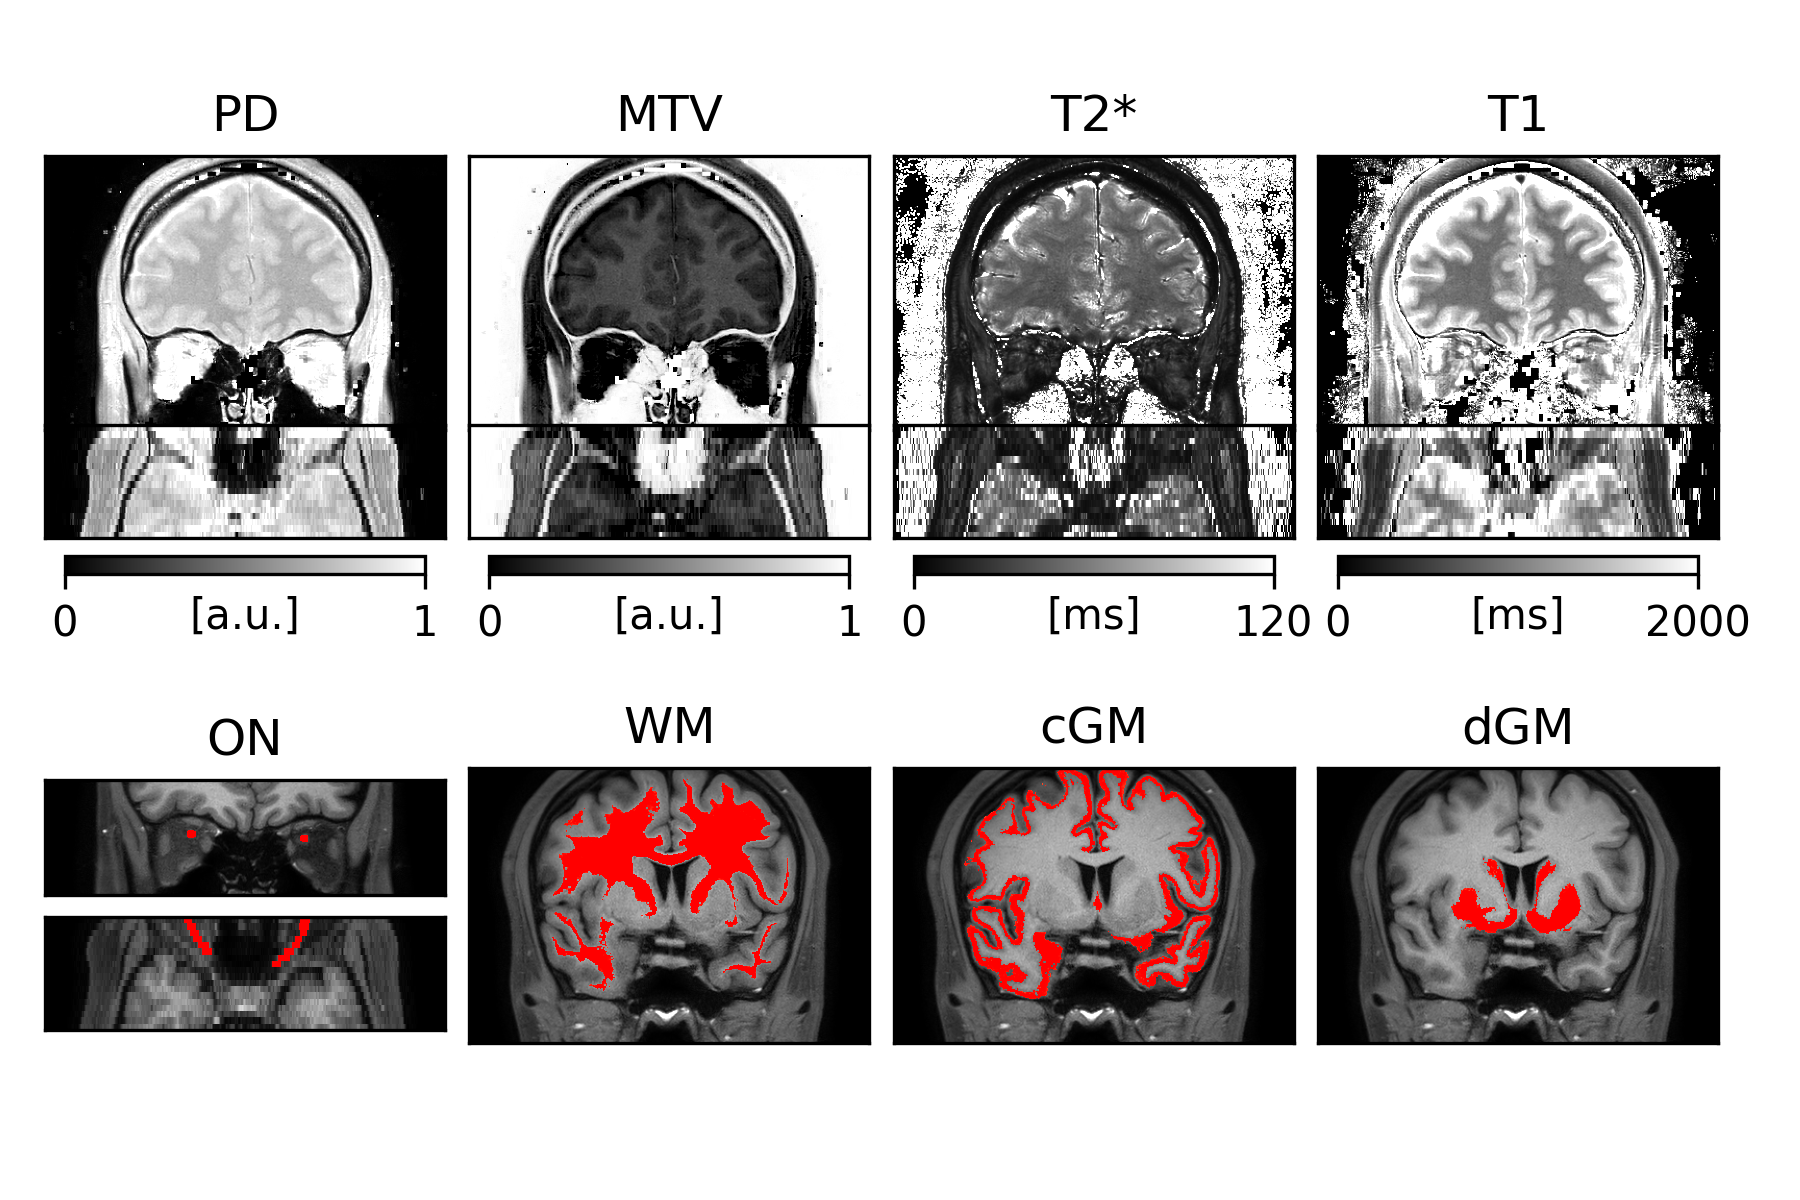

An overview of PD, MTV, T2* and T1 quantitative maps, together with ON, WM, cGM and dGM masks, is displayed in Figure 1. Distributions of regional values are shown in Figure 2. Laterality tests are reported in Figure 3, with significant differences observed in PD ($$$p=0.003$$$), MTV ($$$p=0.003$$$) and T1 ($$$p=0.031$$$) between left and right ON; the same significant trends were observed between left-right fronto-temporal WM ($$$p=0.026$$$, $$$p=0.026$$$, $$$p=0.025$$$, respectively). CV scores are reported in Table 1, with CVs below 10% observed for all metrics and all tissues except for MTV, where CV of up to 28% was calculated.

Figure 1. Examples of quantitative maps and regional masks for a single subject. Top row: PD, MTV, T2* and T1 quantitative maps coronal and axial slices. Bottom row: ON (coronal and axial slices), WM, cGM and dGM masks. The ON masks have been dilated for better visibility.